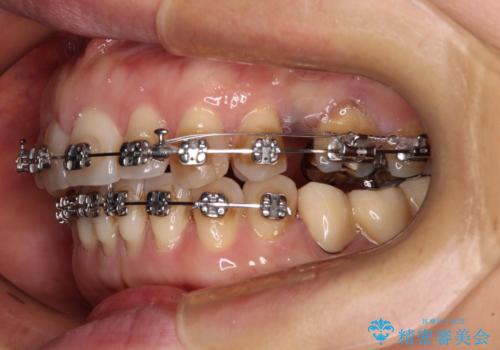

- 矯正装置

- メタルブラケット

右上小臼歯は銀歯が装着されており、ワイヤー矯正の装置が装着できないため、事前に仮歯に変えてから矯正治療を行い、その後オールセラミッククラウンにて補綴治療を行いました。